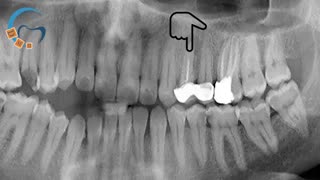

ارتودنسی ثابت و متحرک نامرتبی دندانی و دیپ بایت شدید بدون کشیدن دندان